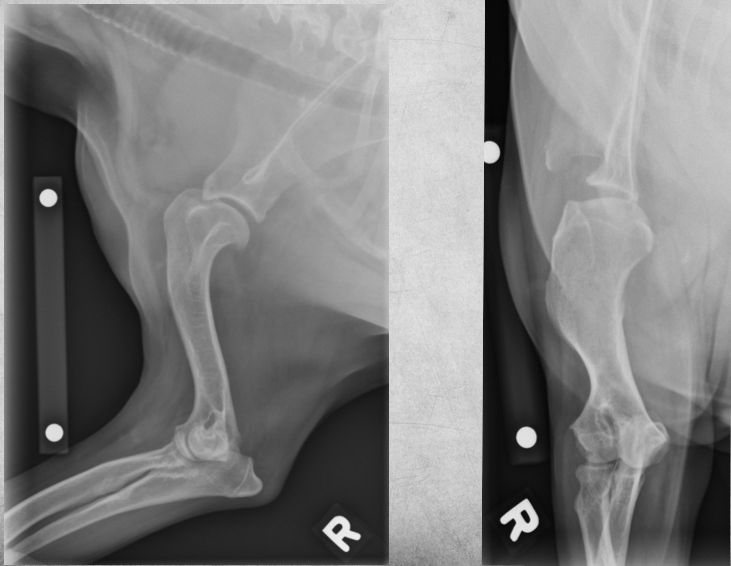

5 months old female Bernese Mountain dog

Played ball with other dogs the previous day

Weight-bearing lameness of left pelvic limb

Mild widening of the left tibial apophyseal physis and small fragment visible at distal portion ->

tibial crest avulsion fracture of growth plate in 5m large breed dog

analgesia and hope it heals okay